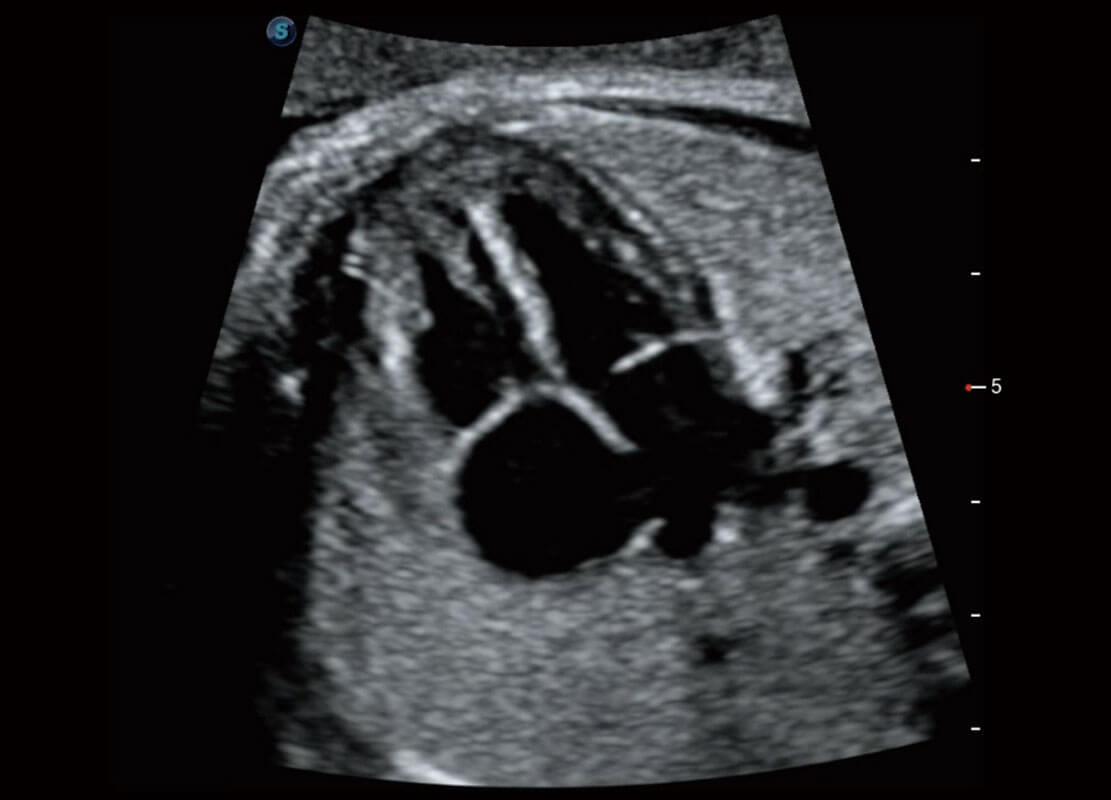

• 早孕-胎心

• 高分辨率容积成像-早孕胎儿